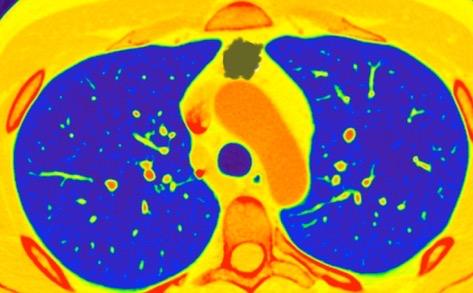

Borramiento parcial por Ca. epidermoide.